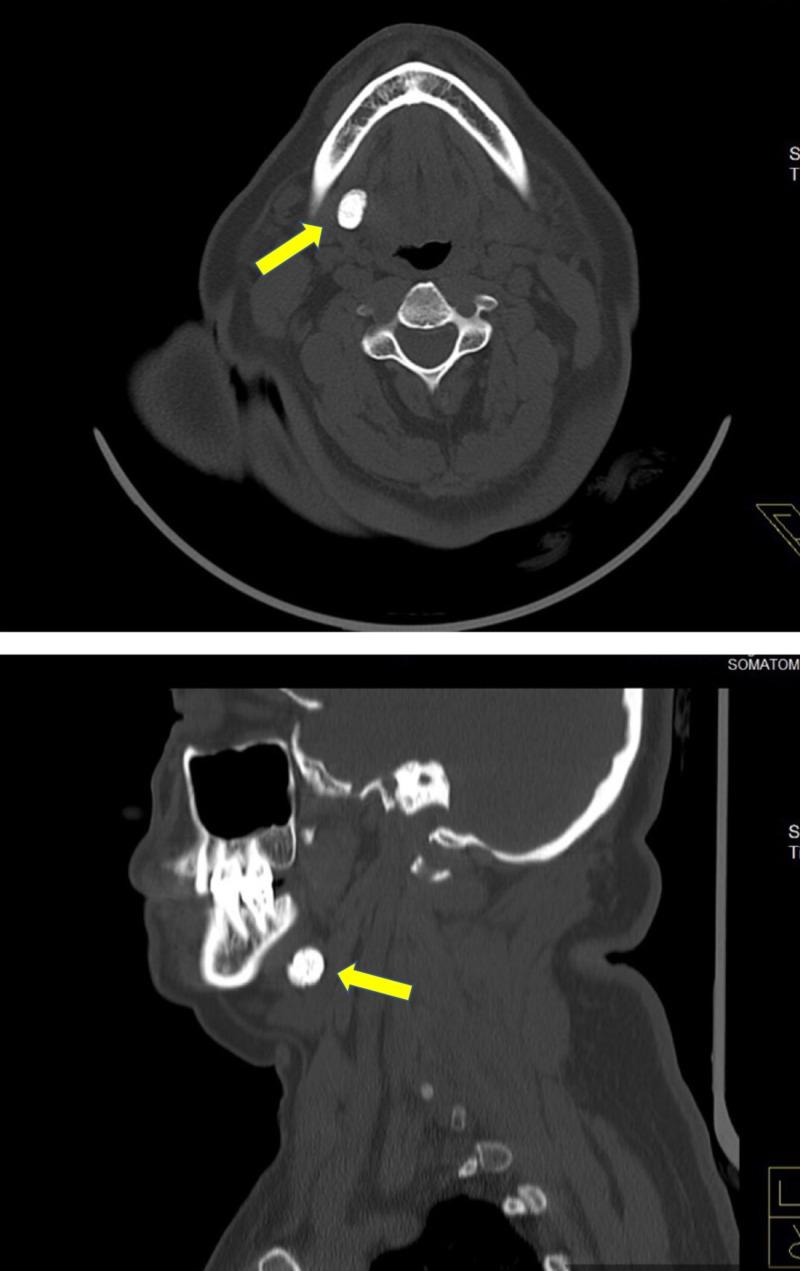

Sialolithiasis is the formation of calcific concretions within the parenchyma or ductal system of the major or minor salivary glands, but it most commonly affects the submandibular salivary gland. Sialolithiasis usually occurs in adults aged 30 to 60 years and causes pathognomonic pain during meals. The treatment of sialolithiasis depends on the size and location of the calculi. We present two cases of sialolithiasis of the submandibular gland managed via the intraoral and extraoral approaches, depending on the position of the calculi.